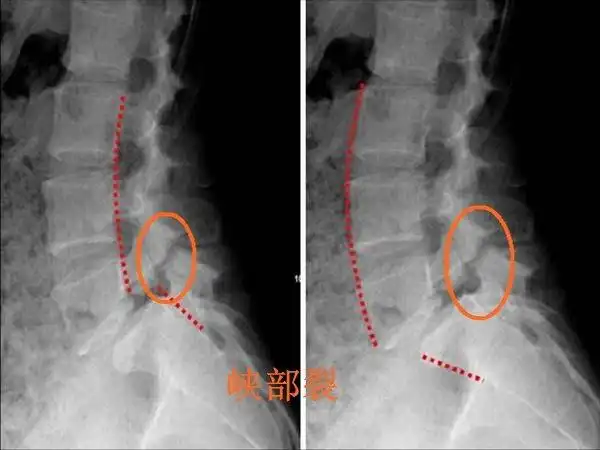

滑脱连线_峡部裂副本_副本.jpg